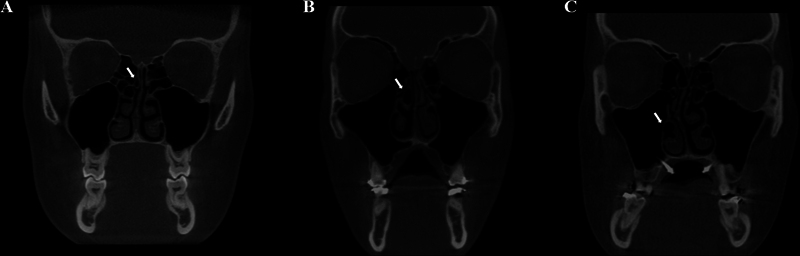

Methods: There were 297 CBCT exams assessed by two examiners who evaluated the presence of CB (> 50% pneumatization of the turbinate's height), NSD (deviation point of the nasal septum and crista galli angle >9 o ), and mucosal thickening of maxillary sinuses (mucosa around the sinus walls > 3 mm in height). The association between CB and side, NSD, mucosal thickening of the maxillary sinuses, sex, and age were evaluated by the chi-squared and Fisher's exact tests (α = 5%).

Results: A total of 208 CB was found, corresponding to 11.7% of the evaluated turbinates, being more prevalent in the middle one ( p  < 0.0001). Considering all exams, 132 (44.4%) had at least one CB. There was an association between the presence of middle left CB with NSD ( p  = 0.028). No other significant associations were found ( p  > 0.05).